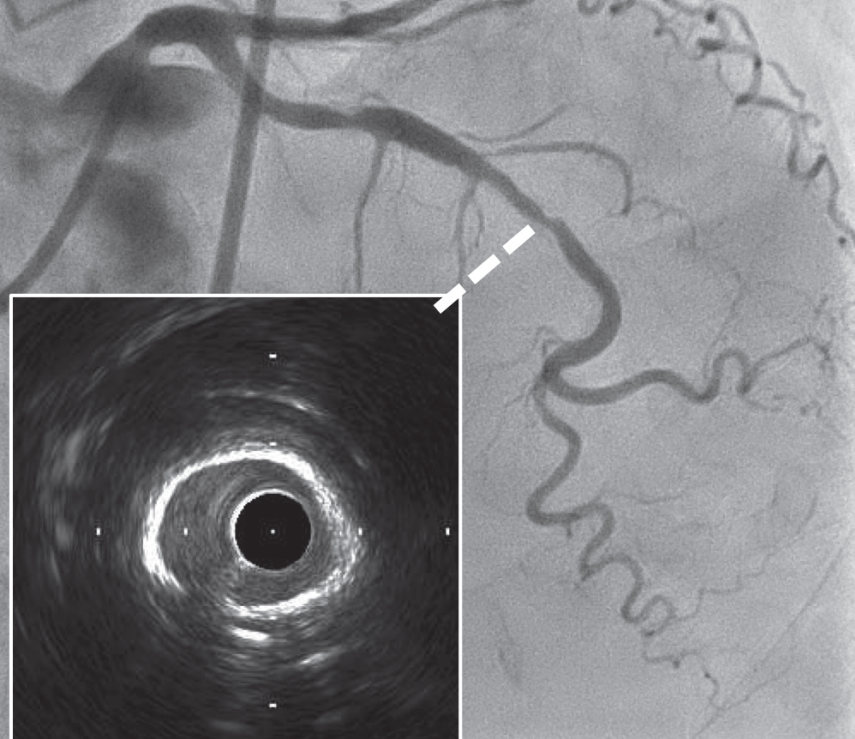

IVUS导管嵌顿可能由于支架钢梁嵌入IVUS导管快速交换口(图11A)、IVUS导管被过度推入严重狭窄部位、或导丝弯曲或扭结导致嵌顿。当然,这种并发症不仅可能发生在IVUS导管上,还可能发生在OCT和OFDI导管上。腔内影像导管嵌顿可能发生在具有第二管腔的短快速交换段导管中。嵌顿的处理方法因发生原因而异。此过程的流程图如图12所示。在严重狭窄导致嵌顿时,术者应尝试通过扩张病变部位来移除导管,或者如果可能的话,使用圈套器在尽可能靠近嵌顿部位的位置抓取被嵌顿器械。如果嵌顿原因是与导丝相关,术者应在推送IVUS导管以纠正导丝弯曲后,再尝试拔除IVUS导管,将 IVUS 导管和导丝一起缓慢撤出。本文重点关注支架钢梁嵌入IVUS导管快速交换口的情况,这是IVUS导管嵌顿中最常见的情形。

图11 IVUS导管嵌顿发生机制的实验图像。

支架植入后IVUS导管嵌顿的实验图像(A)。送入小直径球囊或微导管时的实验图像(B)。导管头端紧贴着支架快速交换口,没有多余空间,导致支架钢梁嵌住IVUS导管

关于支架钢梁嵌入IVUS导管快速交换口的情况,Hiraya等人报告称,IVUS导管嵌顿的发生,在非常迂曲的病变、严重钙化的病变、第三代药物洗脱支架以及支架直径≤2.5mm时较高。IVUS导管快速交换口端嵌顿与其他类型的IVUS导管嵌顿不同,其特征在于,在发生嵌顿后,IVUS导管容易向远端推送,但在回拉时,IVUS导管会在同一位置嵌顿。